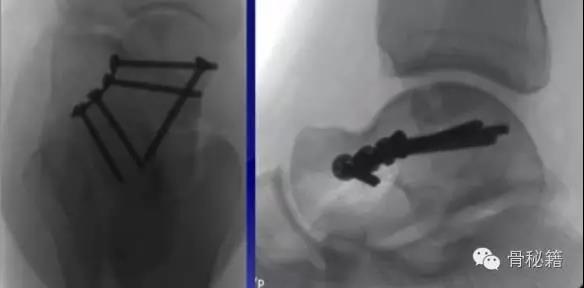

手术指证移位的体部骨折和II-IV型(2mm以上)的颈部骨折移位

手术入路1、内侧入路比较安全,注意大隐静脉和隐神经

骨折十分粉碎时可采用内踝截骨事先可进行螺钉的拧入,类似鹰嘴截骨

2、外侧入路

对于颈部的骨折,如果一侧钢板的位置不佳,则容易造成另外一侧的骨折裂开所以最好的固定是一侧用钢板固定,另外一侧可采用螺钉进行加压,避免另外一侧开口